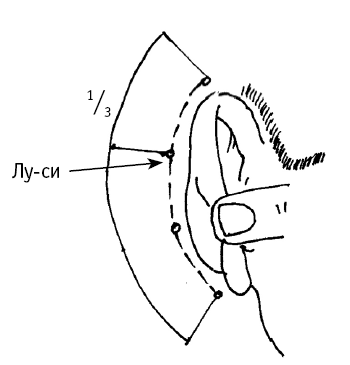

Точка используется так же повышении давления при головной боли, головокружении, судорогах, шуме в ушах, снижении остроты зрения из?за постоянного повышения давления. черепа») находится на 1/3 длины дуги за ухом, считая от верхней точки дуги (рис. 3, д). На точку воздействуют при головных болях, шуме в ушах, бессоннице, чувстве страха, боли в грудной клетке, рвоте (вызванной повышенным давлением).

Точка предназначена также для лечения всех болезней уха (снижение слуха, боль в ухе), а также для уменьшения жара и лихорадки в теле